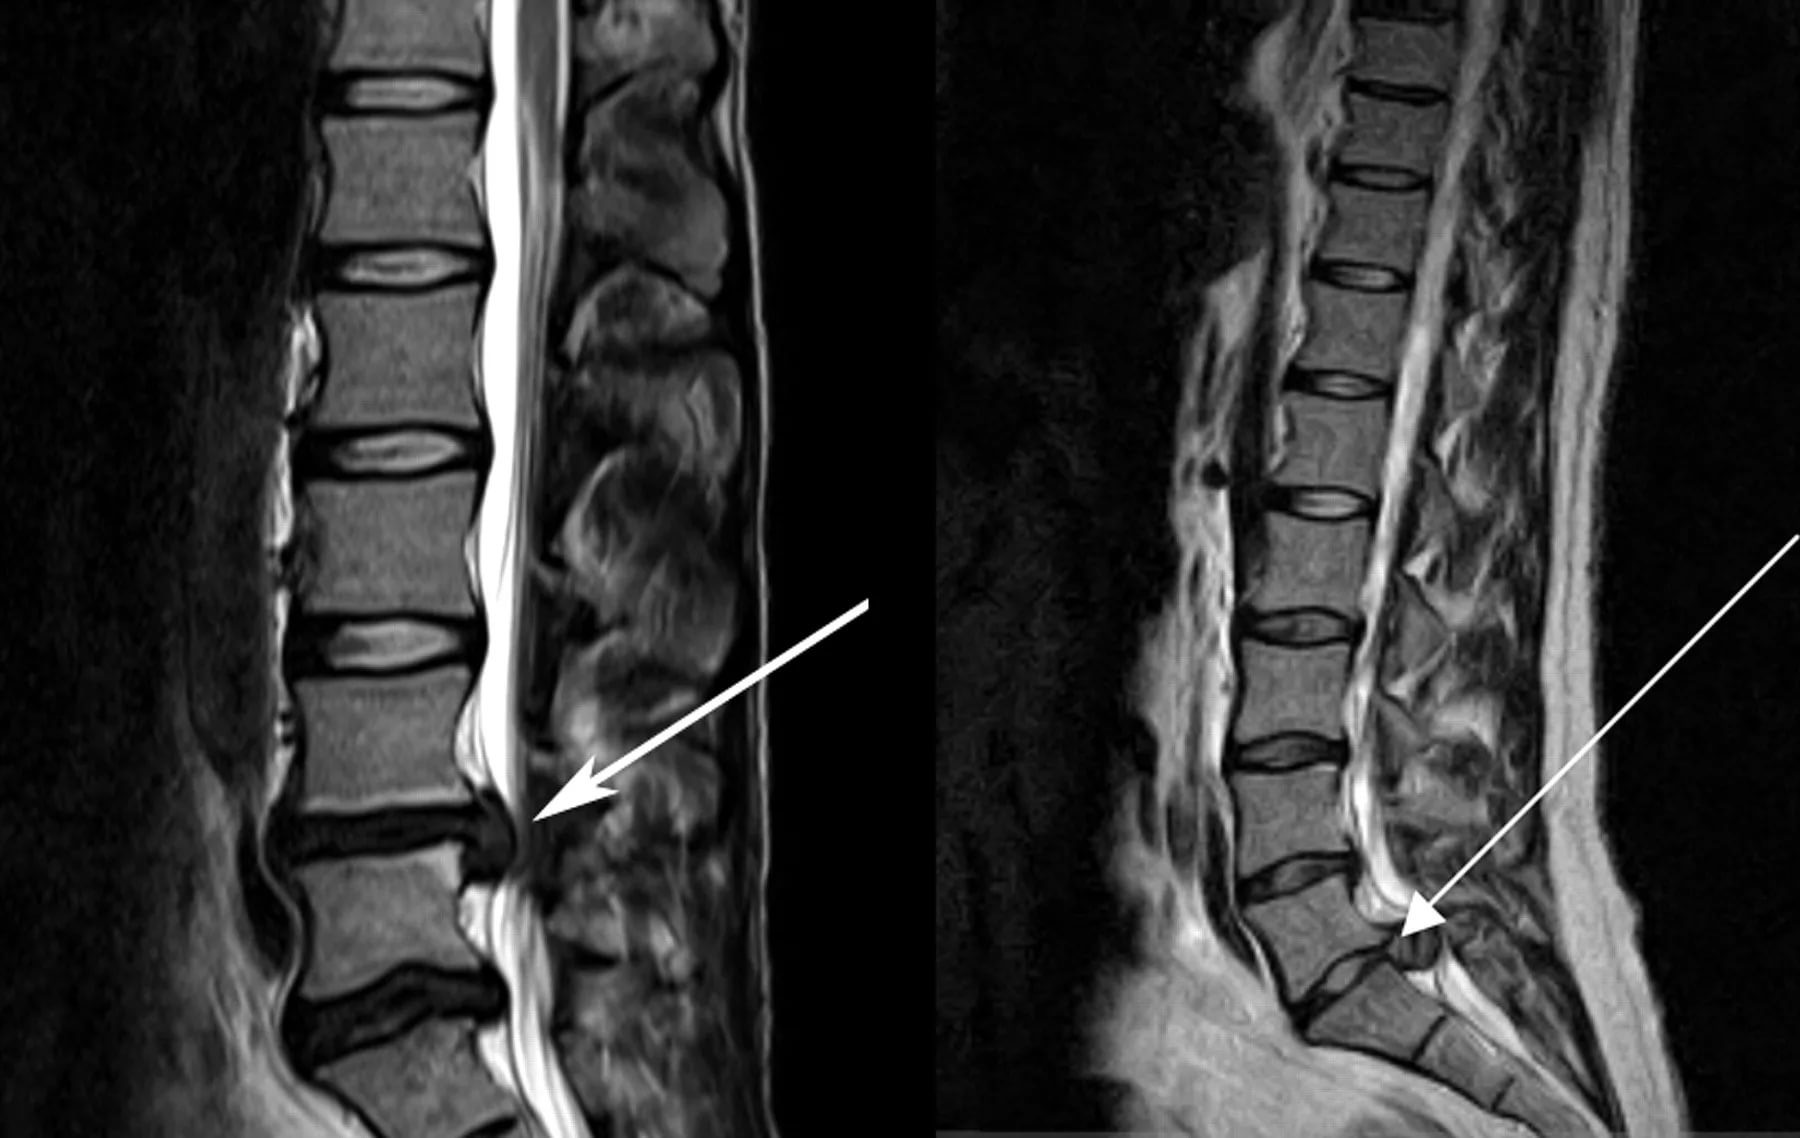

- Рентгенография позволяет увидеть косвенные признаки остеохондроза, такие как сближение позвонков. Однако состояние межпозвоночного диска не отображается, для этого назначают КТ или МРТ. Эти методы также помогают диагностировать радикулит.

- Защемление нерва определяется с помощью электронейрограммы, МРТ и КТ. Мануальный осмотр также может быть информативным, так как компрессия может снижать рефлексы и чувствительность.

Для выявления различных новообразований в спинном мозге, позвоночнике и мягких тканях проводят магнитно-резонансную и компьютерную томографию.